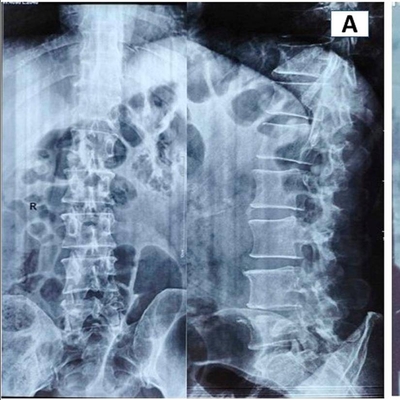

Click on an image below to view more info.